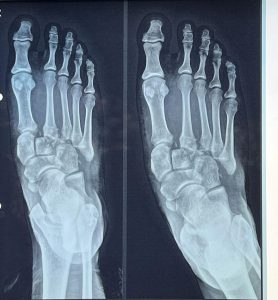

🦴 Lisfranc Injury (Midfoot Fracture) Treatment in Ahmedabad, Rajkot & Surat

By Dr. Ankit Kamothi – Foot & Ankle Specialist in Gujarat 🦴 Lisfranc Injury (Midfoot Fracture) Treatment in Ahmedabad, Rajkot & Surat By Dr. Ankit Kamothi – Foot & Ankle